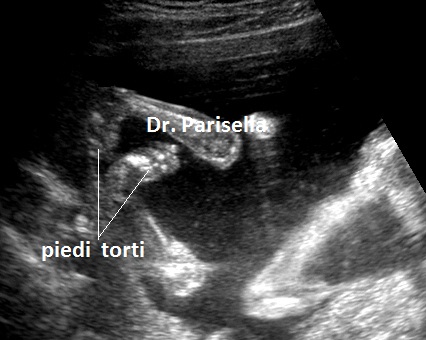

piede torto

Si manifesta con severa micromelia, ipoplasia toracica, piede torto, palatoschisi, micrognazia, pollici ed alluci addotti, scoliosi.